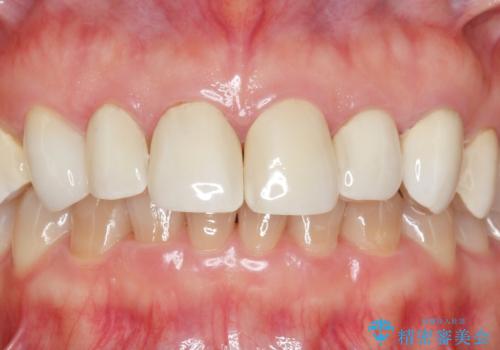

ラミネートよりもより透明感の再現性の高いジルコニアクラウンの出来に喜んでいただくことが出来ました。